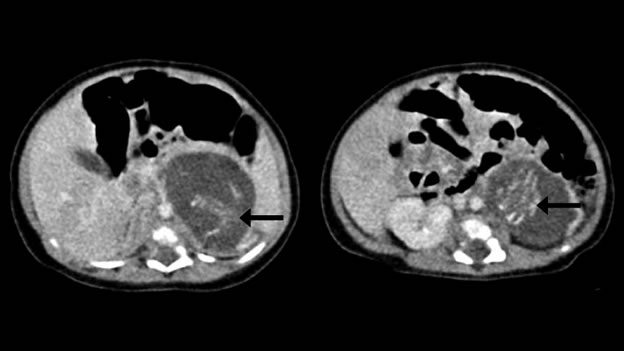

La masa de tejidos fue vista en un ultrasonido en la semana 37, y los hechos después de que la niña nació mostraban que la masa abarcaba dos centímetros entre su bazo y riñon izquierdo.

Las dos formas encontradas tenían diferentes pesos pero igual desarrollo de órganos, coincidente con un feto de 10 semanas de gestación. Tenían espinas dorsales y “genitales externos ambiguos”, aunque no contaban con cráneos.

Los festos estaban unidos por cordones umbilicales en lo que parece ser una masa de placenta. Cada uno tenía cuatro miembros, piel, costillas, intestinos y tejido cerebral primitivo, de acuerdo con un estudio publicado este mes en el Hong Kong Medical Journal.